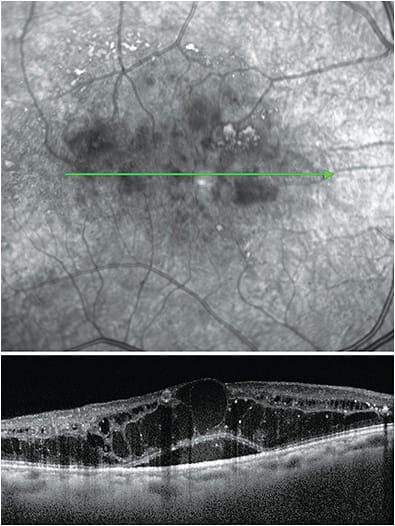

The advent of OCT has dramatically improved our ability to detect and manage DME, rather than the presence of CSME, a diagnosis made by macula slit lamp examination. For example, OCT has opened our eyes to focal and diffuse DME. Some patients with focal DME, characterized by localized leakage from microaneurysms and 20/20 vision, may be monitored closely with three-month follow-up visits rather than treated. While those with diffuse DME, leakage that involves the entire circumference of the fovea, are treated.

Currently, DME is categorized as center vs. non-center-involved, based on SD-OCT. Center-involved DME is characterized by loss of foveal contour, cystoid macula edema involving the center of the fovea, neurosensory detachment involving the center of the fovea and increased central subfield thickness.

Until recently, DMI was identified as a cause of central vision loss in diabetic patients. It is an irreversible vision-threatening complication in cases with or without DME. The condition is characterized by the occlusion and loss of the macular capillary network or capillary dropout, according to the American Journal of Ophthalmology.

The availability of OCT-A has shown several new clinical findings in DMI patients. These clinical signs are paramacular areas of capillary nonperfusion, impairment of the choriocapillaris flow and enlargement of the foveal avascular zone (FAZ). Abnormalities in the structure or perfusion of the FAZ results in vision impairment and a poor prognosis because the condition cannot be treated.